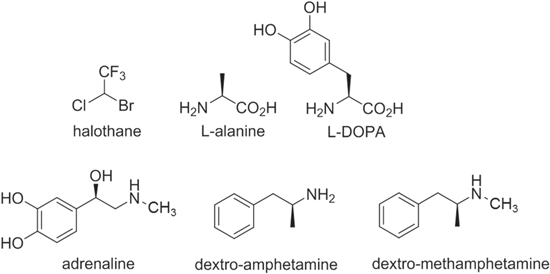

To address in detail the chirality of molecular structures, it is important to pay heed to the complexity of the system, avoiding a compromise of fundamental symmetry arguments by unphysical representations. The spatial dimensions of the individual molecules play a role that is often overlooked. Some relatively small chiral molecules associated with medical or health issues, governed by their left–right-handed form, are illustrated in figure 3. Chiroptical effects in the visible, near-UV and near-IR regions necessarily relate to the engagement of electromagnetic fields with material electronic configurations, and as molecular size increases the most prominent forms of optical response are usually less associated with the entirety of the molecule, more with specific 'chromophore' regions of locally distinctive electronic response (the only significant exceptions are molecules such as polyenes with an extensively delocalized electronic structure). Such chromophores are not directly identifiable with the 'chiral centers' designated as R or S (from the Latin rectus or sinister) in the well-established rules for identifying and classifying chirality in organic compounds [22].

Figure 3. Molecular structures of some simple chiral compounds that can be formed in either right-or left-handed enantiomeric form, and whose handedness (with the exception of halothane, the smallest) significantly affects their medical action. Wedge-shaped lines represent bonds projecting forwards, in front of the figure plane; shortened lines signify bonds projecting backwards.

Standard image High-resolution imageAnother, more general aspect deserves mention: the multiplicity of nuclear framework vibrational modes that generally rise in tiers within every electronic state. For example, the relatively small drug molecule L-DOPA with 22 atoms, illustrated in figure 3, has sixty distinct vibrational frequencies. As a result of this feature, the frequency dispersion properties of all but the very smallest molecules (and even for those, except at very low temperatures) are associated with significantly broad and often overlapped line-shapes. Due to computational complexity, vibrational structure is seldom considered in computing molecular response functions, even today, although a parametric dependence on various stable or semi-stable configurations can be taken into account in density functional theory calculations [23]. Nonetheless, the specific effect of nuclear vibrations is customarily ignored even in calculating molecular polarizabilities—despite their importance being previously flagged in numerous publications: see for example [24]. There is no reason to suppose that such factors should not prove just as significant for the other electronic response tensors associated with chiroptical response.